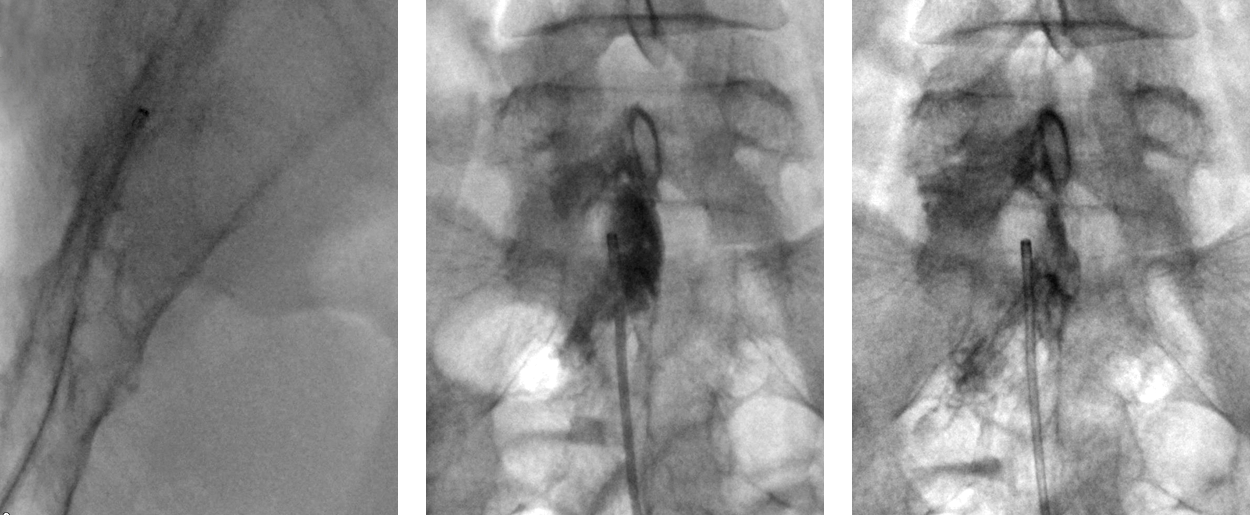

꼬리뼈 쪽에 카테터가 들어갈 수 있도록 가이드 바늘을 삽입

신경 부위에 접근

조영제 주입 후 카테터를 통증 부위 및 시술 부위까지 넣어 좁아진 공간 확장

카테터를 통해 염증, 유착, 경막외 지방 등 신경을 자극하는 원인을 제거하여 유착을 완화

치료가 끝난 후 카테터를 빼고 절개부위를 봉합 시술